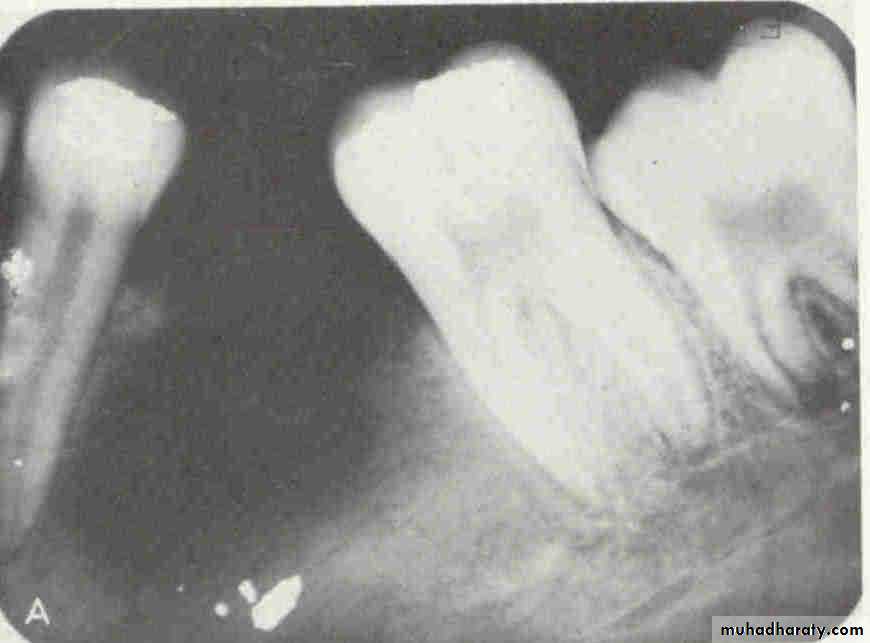

Is the maxillary second premolar (arrows) displaced to the buccal or the lingual?

premolar filmmolar film

premolar bitewing

4The tube head moves distally from the premolar film to the molar film. The second premolar also moves distally, overlapping the first molar more in the molar film. In moving from the premolar periapical to the bitewing, the tube head moves down and the premolar also moves down. The displacement is to the lingual.